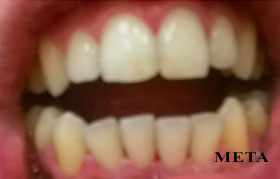

bonding δοντιών

άμεσες όψεις - edelweiss